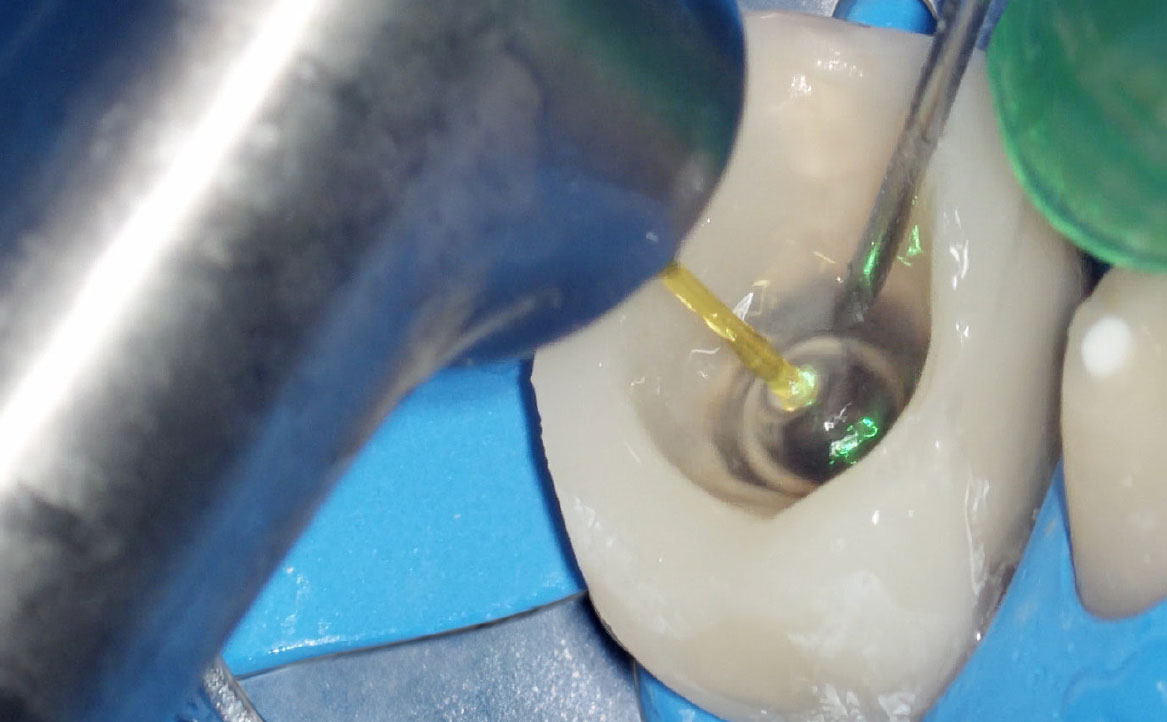

La massima azione microbicida avviene combinando ipoclorito di sodio e laser: una volta inoculato l’ipoclorito all’interno del canale, si porta la fibra (200nm) a circa 1 mm dall’apice (fig. 2), si attiva, quindi, con movimenti circolari in direzione apico-coronale, si percorre il canale in tutta la sua lunghezza. L’operazione, da ripetere tre volte, dura complessivamente 20s e si effettua al termine della fase di strumentazione (fig. 3, 4).